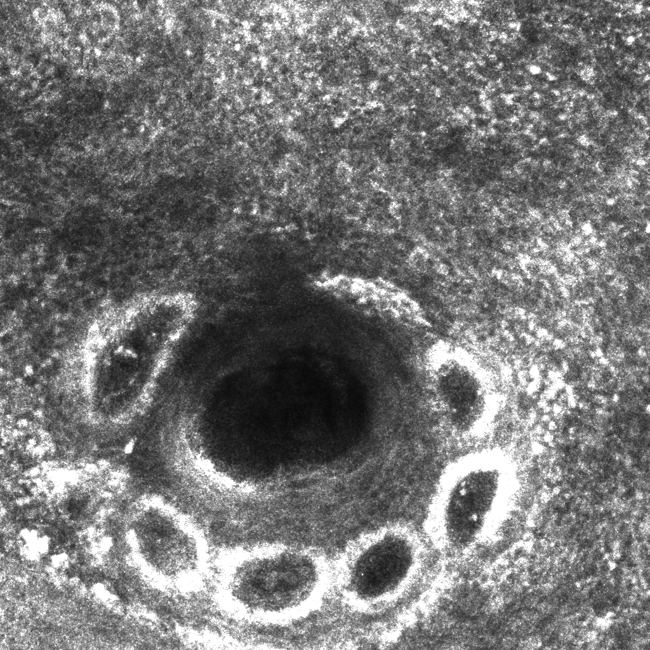

Please review the clinical and dermoscopy images below. What are the three potential diagnoses of flat pigmented lesions on the face, and how do you differentiate between them?

This lesion is a solar lentigo. Confocal imagery: